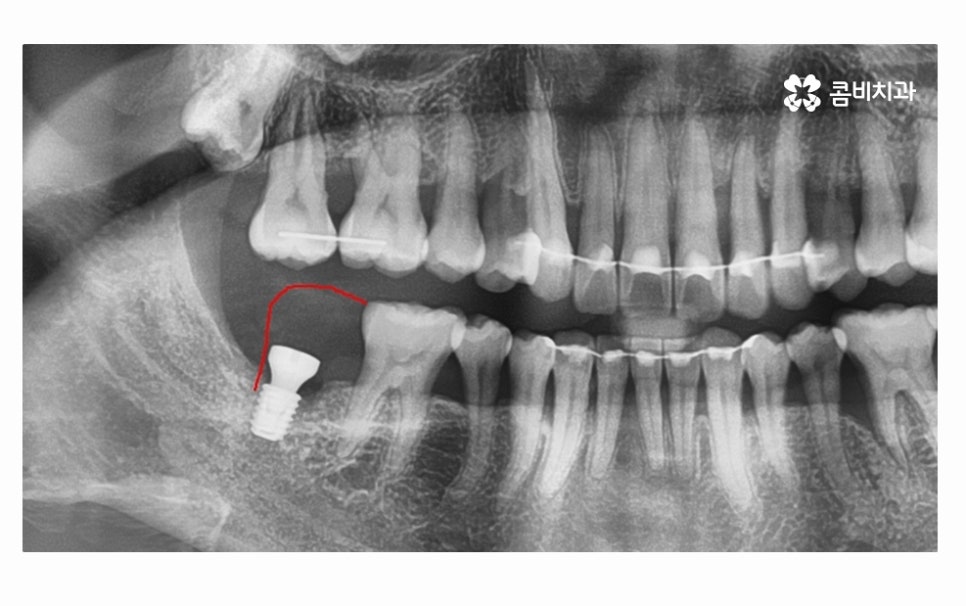

오늘 소개드릴 환자분의 케이스는 치아 상실의 요인이

잇몸질환이 심해져서 치아 뿌리까지 염증이 발생되었고

결국 어금니 발치 까지 이어진 사례라고 할 수 있는데요.

어금니 발치까지 이어지도록 청결 관리에 악영향을 준 요소로는

평소의 식습관이나 칫솔질 부분도 컸겠지만

불규칙한 치열과 옆으로 누운 사랑니도 영향이 컸으며